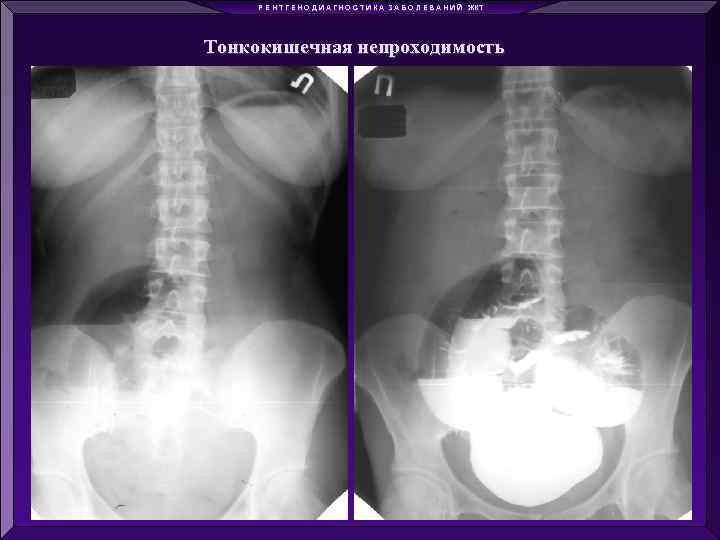

Р Е Н Т Г Е Н О Д И А Г Н О С Т И К А З А Б О Л Е В А Н И Й ЖКТ Тонкокишечная непроходимость

Р Е Н Т Г Е Н О Д И А Г Н О С Т И К А З А Б О Л Е В А Н И Й ЖКТ Тонкокишечная непроходимость